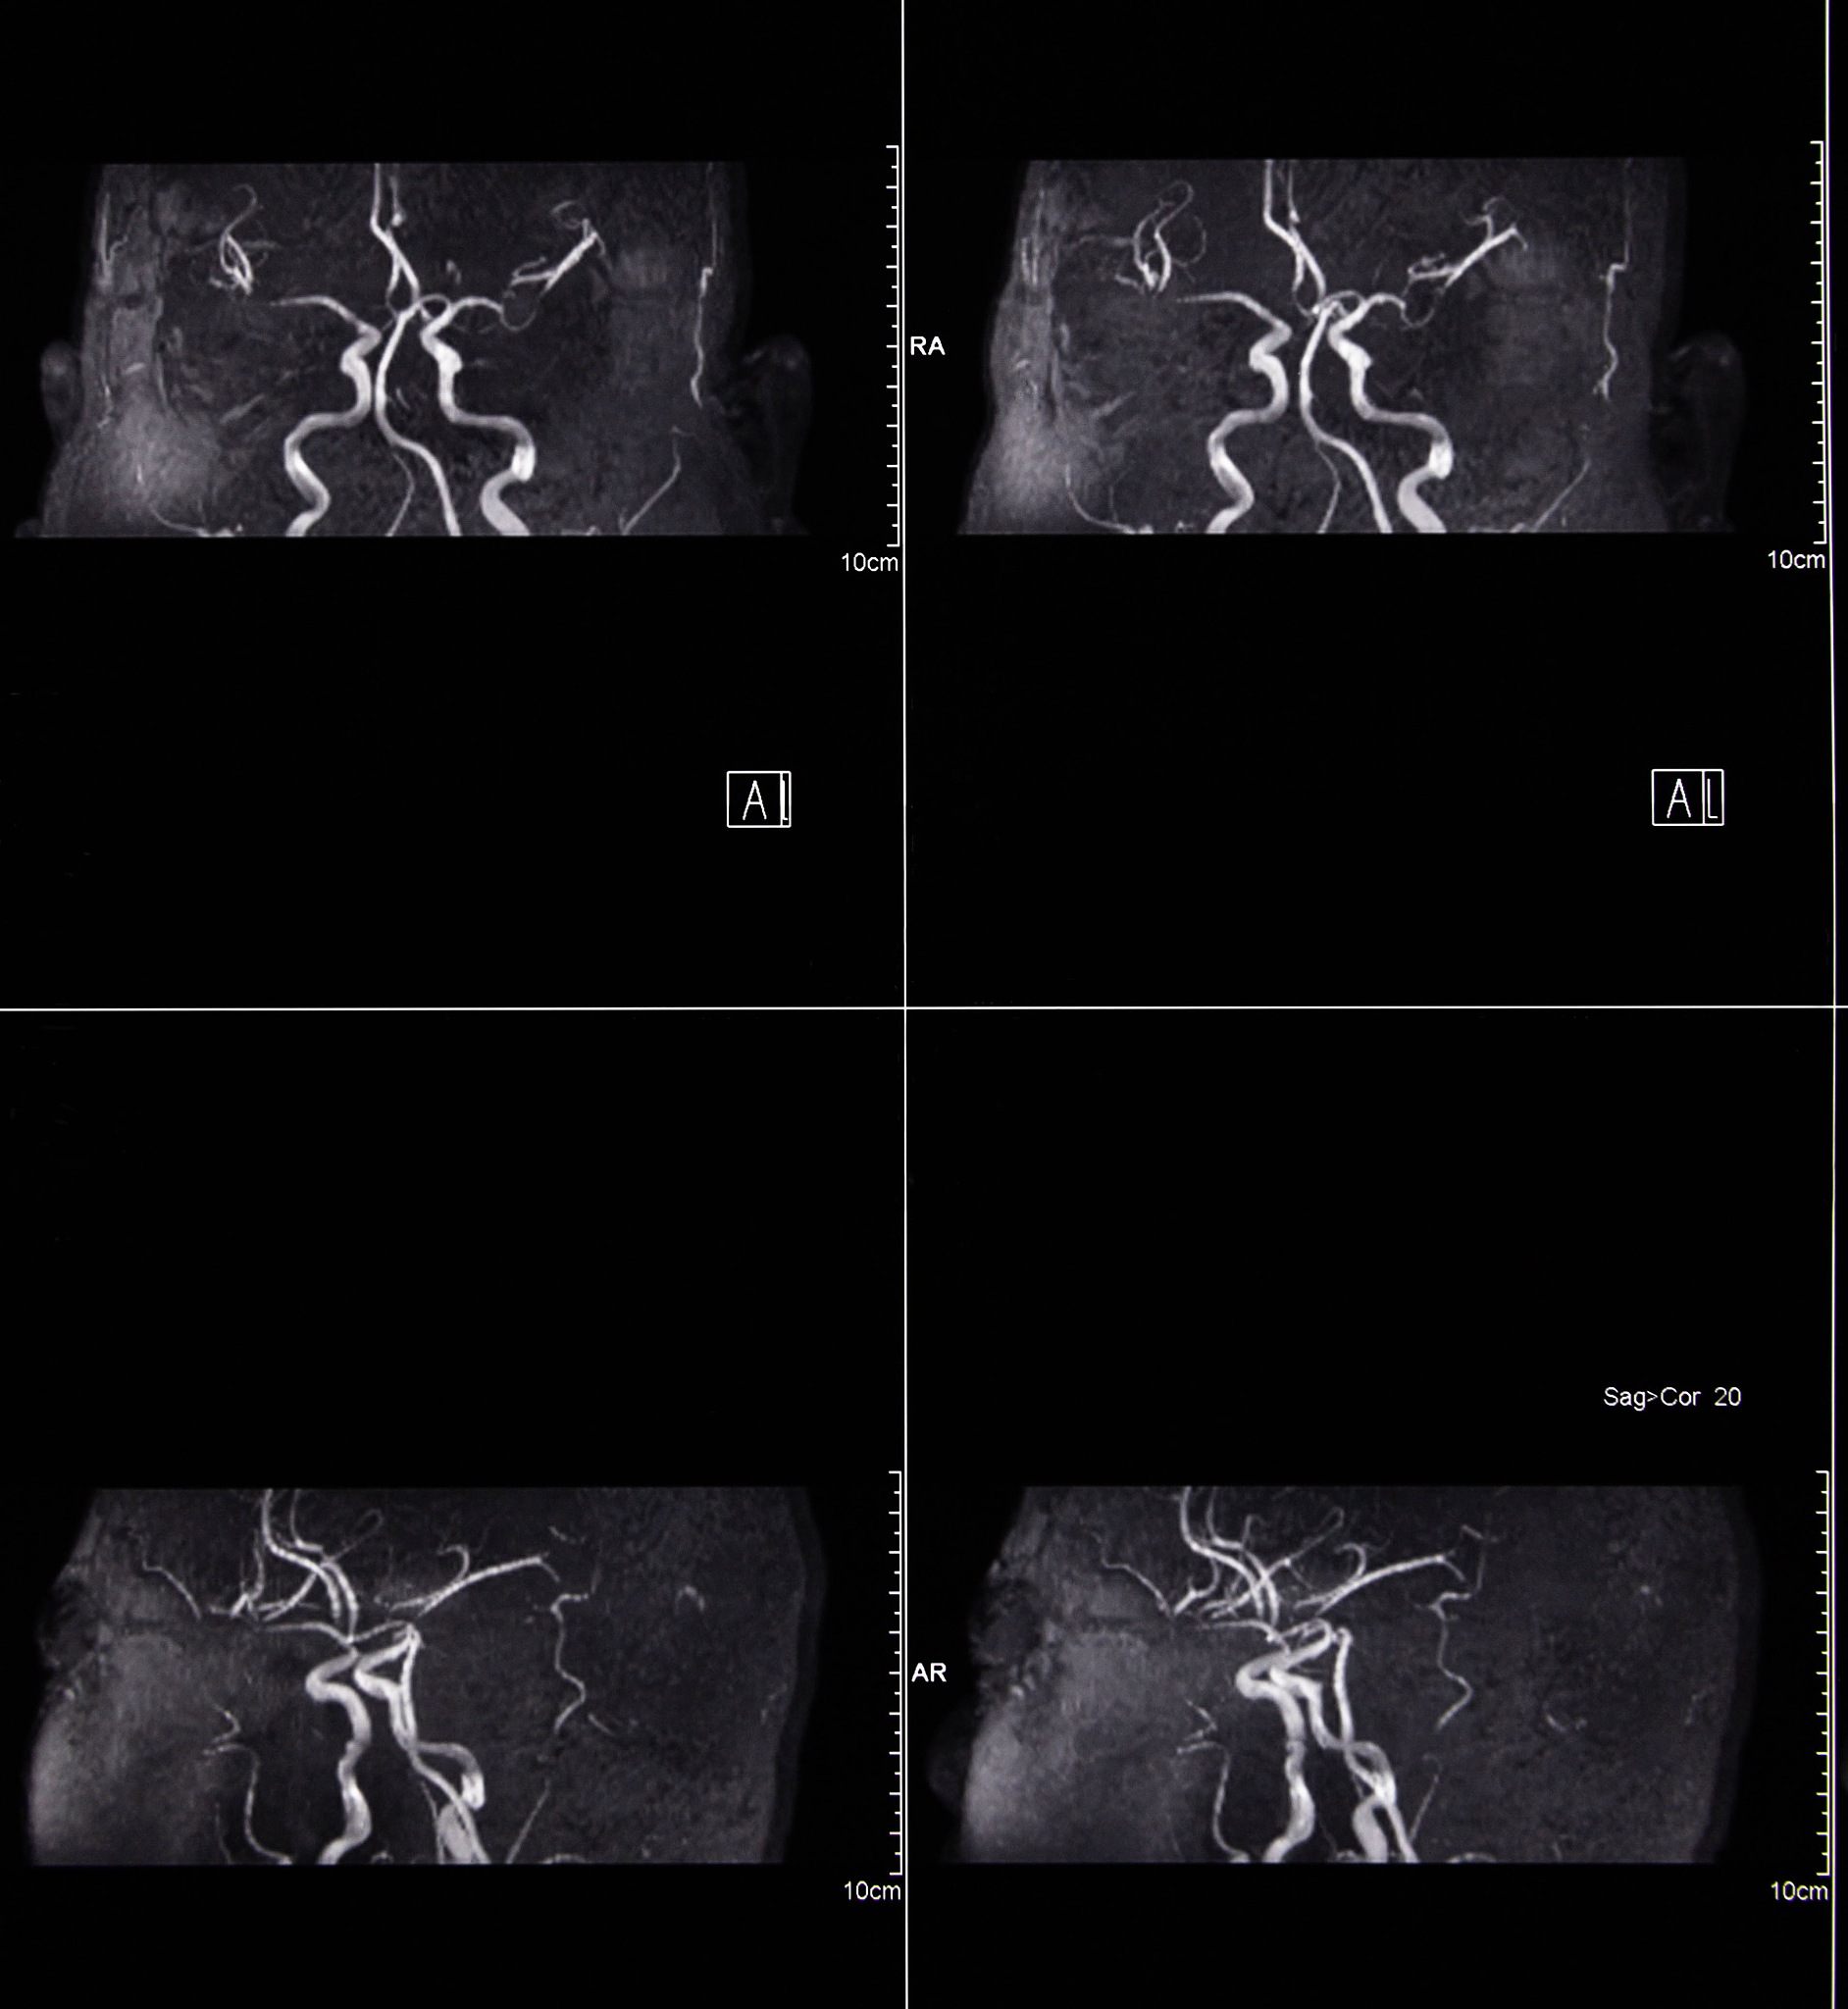

根据经超声造影检查结果,您可能患有右侧颈动脉易损性斑块破裂形成溃疡,同时伴有漂浮血栓形成和右侧颈内动脉起始部中度狭窄。这种情况可能会导致血液流动不畅,增加心脑血管疾病的风险。建议您及时就医,接受进一步的诊断和治疗。治疗方案可能包括药物治疗、手术治疗等。同时,您也需要注意生活方式的改善,如控制血压、血糖、血脂等,保持健康的饮食习惯和适量的运动。